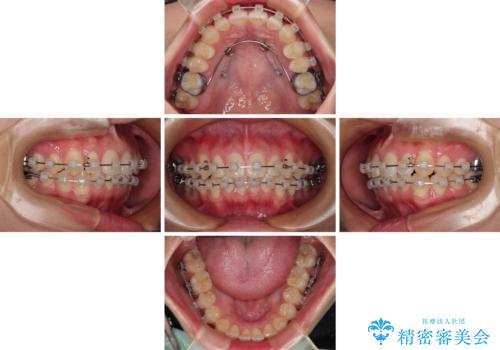

- 矯正装置

- 審美装置

インビザラインでもワイヤー装置でも対応可能でしたが、自己管理の煩わしさの観点から、楽して治療のできるワイヤー装置を選択されました。

抜歯するほどではないものの、やや口元の突出感が気になっていたので、補助装置により上顎臼歯を後方に移動させることで、突出感改善を図ることとしました。

1年弱の短期間で、望み通りのスッキリとした口元に仕上げることができました。